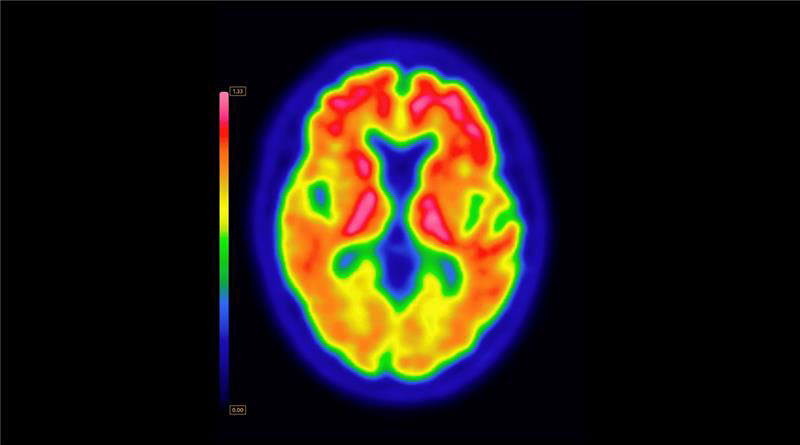

ARLINGTON HEIGHTS, Ill.--(BUSINESS WIRE)--GE HealthCare (Nasdaq: GEHC) today announced that the U.S. Food and Drug Administration (FDA) has approved an updated label for its positron emission tomography (PET) imaging agent VizamylTM (flutemetamol F 18 injection) for beta-amyloid detection. The revised label, effective immediately, expands the indications for use, enables quantitative analysis of Vizamyl scans, and removes significant previous limitations such as monitoring patient response to anti-amyloid therapy.

Up to now, amyloid diagnostics such as Vizamyl have been used to provide a visual assessment of amyloid plaque accumulation in the brain. With quantification now added to the label, clinicians can reach a more objective assessment, using software that enables a calculation of amyloid load, with published research demonstrating that quantification improves diagnostic confidence and consistency among readers1,2,3. In addition, with the removal of a limitation of use for monitoring therapy effectiveness, Vizamyl can also now be used to assess whether the level of amyloid plaques has been reduced sufficiently for the therapy to potentially be stopped.

Vizamyl was first approved in 2013 to estimate beta amyloid neuritic plaque density in adult patients with cognitive impairment. GE HealthCare offers solutions for quantitative analysis of amyloid PET scans including through its MIM Neuro Software platform which has been recently FDA cleared for centiloid scaling.